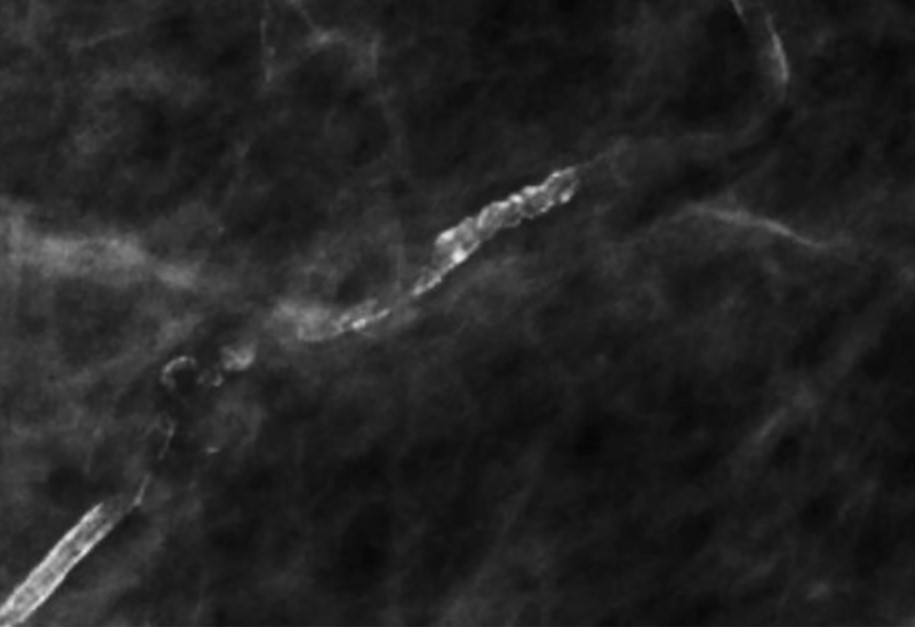

При инфильтрации перидуктальной стромы плазматическими клетками и пролиферации клеток базальной мембраны протоков образуются линейные, стержневидные кальцинаты ориентированные по ходу протоков. Такая картина патогномонична для перенесенного плазмоклеточного мастита (Рис.9).